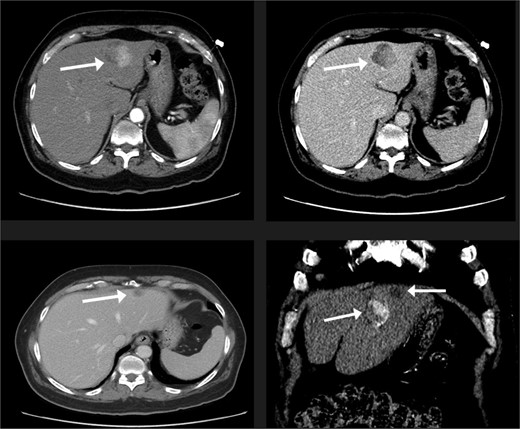

A 74-year-old man with right-handed colon cancer presented at the Emergency Department with a symptomatic anemia following chemotherapy and surgical intervention one year prior to the hepatocellular carcinoma resection. He reported 1-month history of paleness, dizziness, and exertional dyspnea, and fatiguability. Physical examination results were unremarkable. A chest CT angiography did not reveal a pulmonary embolism; however, two hepatic lesions, measuring 3.5 cm and 1.5 cm, in segment II were noted incidentally. Therefore, further laboratory tests were performed; hepatitis C virus was detected with a liver cirrhosis Child-Pugh score indicating class A disease; however, no tumor markers were detected. An abdominal CT revealed the two hepatic lesions in segment II, the larger lesion (3.8 cm × 3.4 cm) demonstrated arterial enhancement and faint washout in the delayed phase (Fig. 1). The smaller lesion measured 1.2 cm × 1.1 cm (Fig. 1). An abdominal MRI was performed to characterize the hepatic lesions: one lesion was consistent with HCC and the second was metastatic from mucinous which was visible previously on imaging at the time of diagnosis of colon cancer (Fig. 2). Furthermore, the biopsy of the two liver lesions confirmed the diagnoses of HCC and metastatic colon cancer. Subsequently, the case was discussed within a multidisciplinary tumor board (MDTB), where the decision was made to perform chemotherapy and trans arterial chemoembolization for the HCC lesion. Upon follow-up evaluation, segment II hepatic lesion size had decreased to 1.6 × 2.4 cm (previously was 3.8 × 3.4 cm) and 1.5 × 1.3 cm (previously 1.2 × 1.1 cm). Consequently, the case was rediscussed in MDTB, and it was decided to proceed with liver resection of the two lesions. Following this, the patient underwent left lateral lobectomy, common hepatic artery dissection, porta hepatis lymph node dissection, and cholecystectomy. Postoperative pathology showed a residual 2.3-cm-sized differentiated HCC and a metastatic colonic-type adenocarcinoma with a mucinous differentiation which was 1.2 cm in size. The two lesions measured 0.7 cm apart (Fig. 3). All lymph nodes dissected from the porta hepatis, and the common hepatic artery were positive for metastatic colonic type adenocarcinoma. The patient’s postoperative course was unremarkable, and he was discharged 12 days later. Following a discussion within the MDTB, it was decided to continue adjuvant chemotherapy.

The liver lesions in segment II. The largest lesion is 3.3 × 3.4 cm and demonstrates arterial enhancement and faint washout in the delayed phase. In the portovenous phase, the smaller lesion is 1.2 × 1.1 cm.